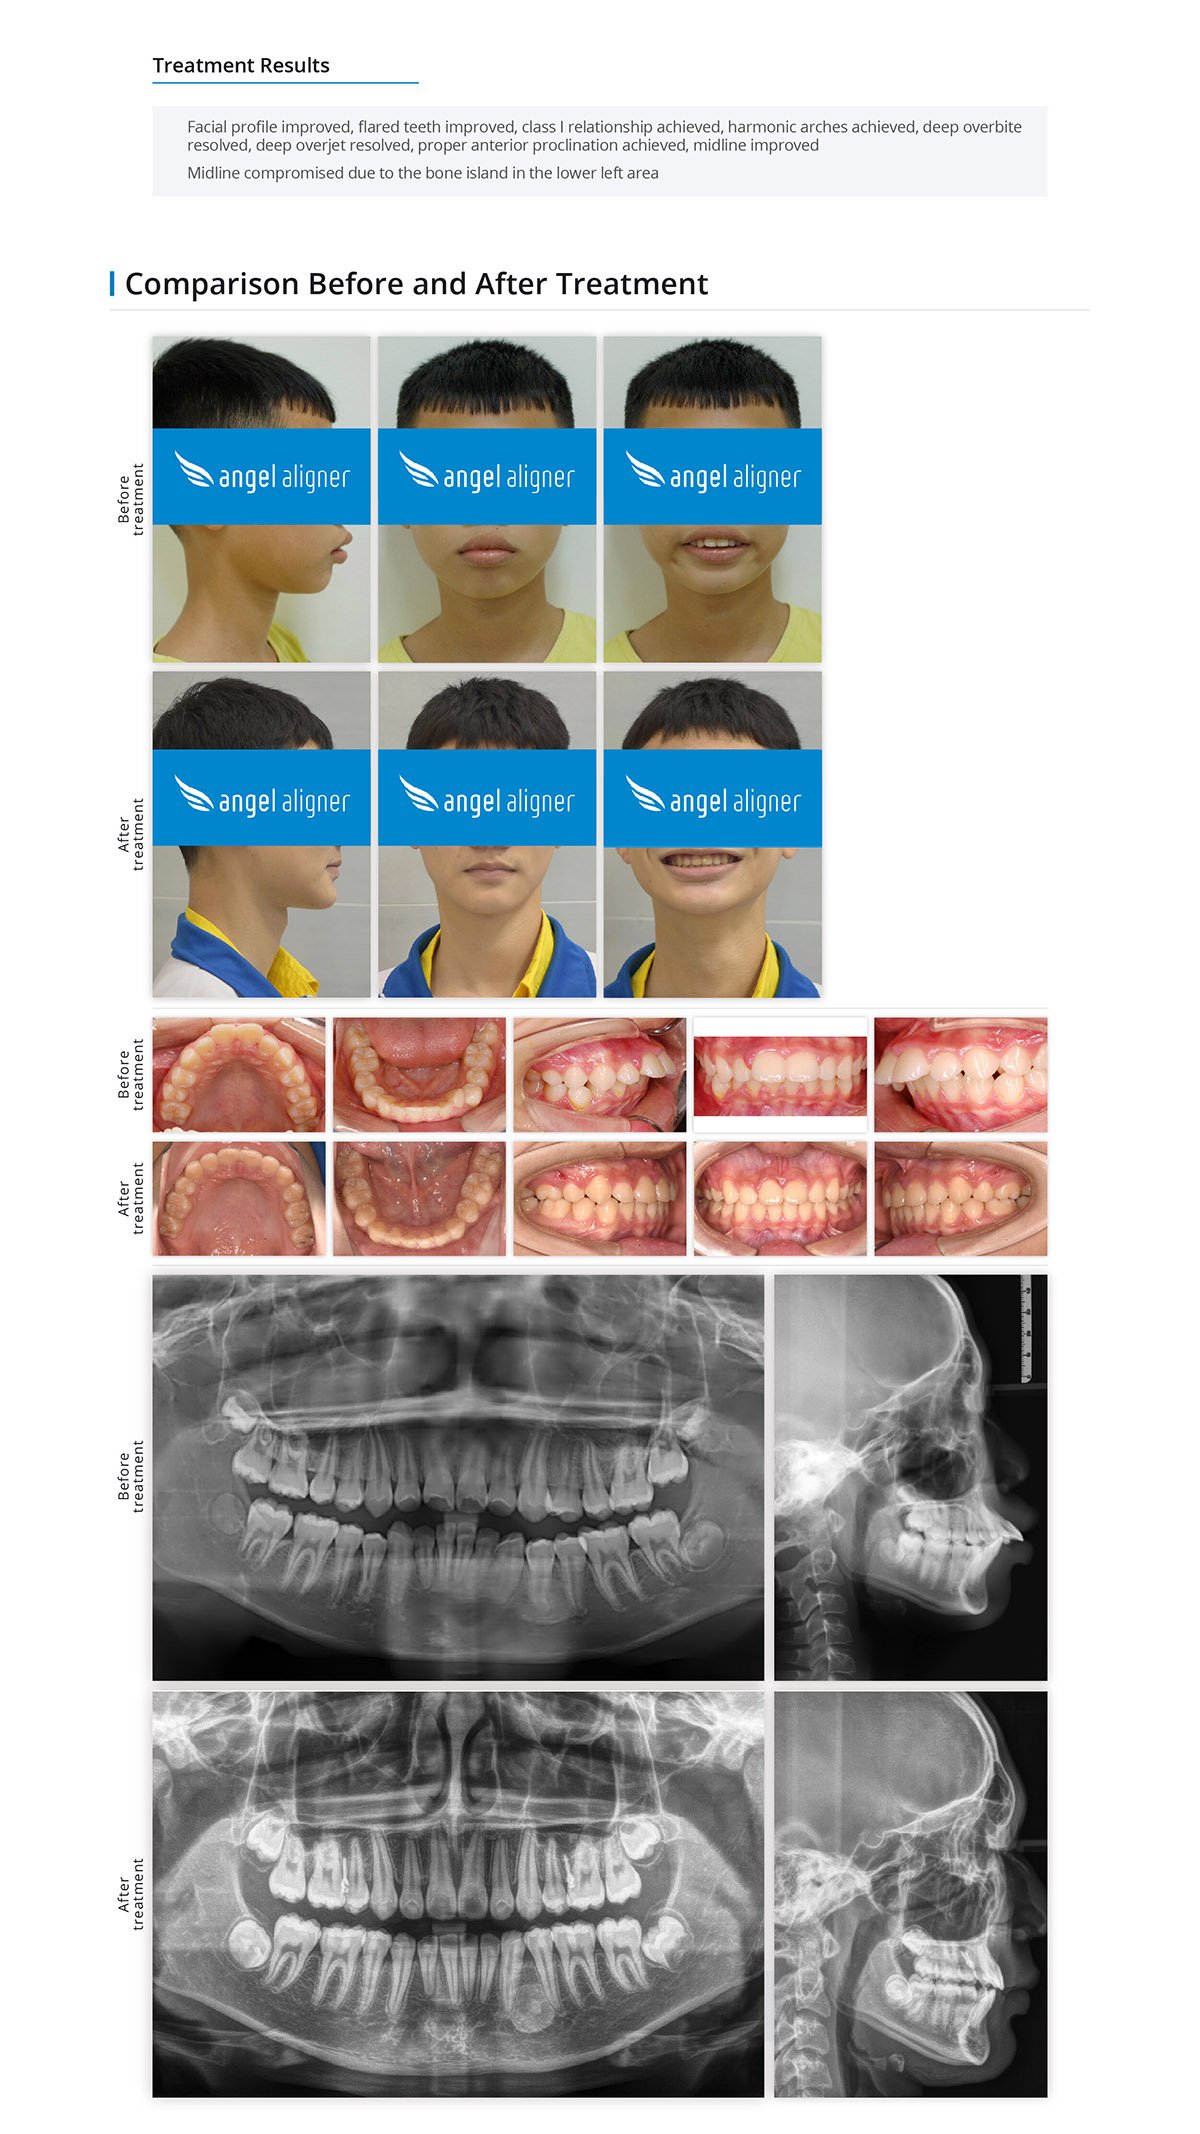

05

Patient Information

Female, 23 years old

Permanent dentition

Angel Aligner Classic

Total treatment time: 32 months